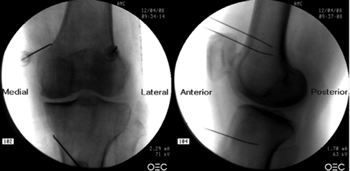

Figure 3